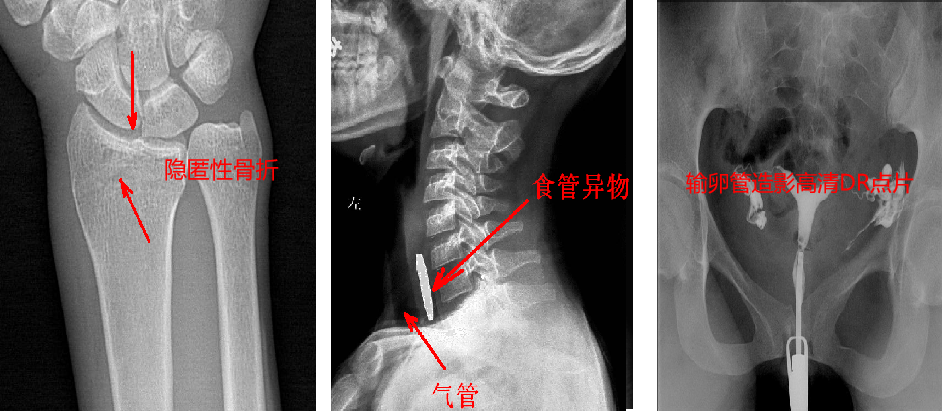

靜態(tài)DR最大的缺陷來自于盲拍,因此造成誤診發(fā)生率高,是保證診斷準確性的巨大阻礙因素。在靜態(tài)拍片中,部分特殊病灶容易被遮掩而導(dǎo)致漏診,在一些特殊造影上需要憑借醫(yī)生的臨床經(jīng)驗才能獲取有效影像。而動態(tài)DR依靠可視化高速高清點片功能,改變了傳統(tǒng)的盲拍模式。動態(tài)DR在低劑量數(shù)字透視的情況下,能夠進行疑似病灶部位點片,極速精準獲取有效信息,同時可即時回放視頻信息,在臨床上極大地提高了病變的檢出率,降低漏診誤診。

與此同時,動態(tài)DR的成像視野與精度也勝于靜態(tài)DR。動態(tài) DR17×17 英寸方形幅面進行動態(tài)成像,能夠?qū)鹘y(tǒng)動態(tài)造影幅面小的問題全部解決,同時由于幅面較大,臨床操作技師能夠在一個大的幅面下觀察診斷,當看到病變部位時實時高清點片,從而很好地捕捉到病變點,也大大降低了檢查時間。